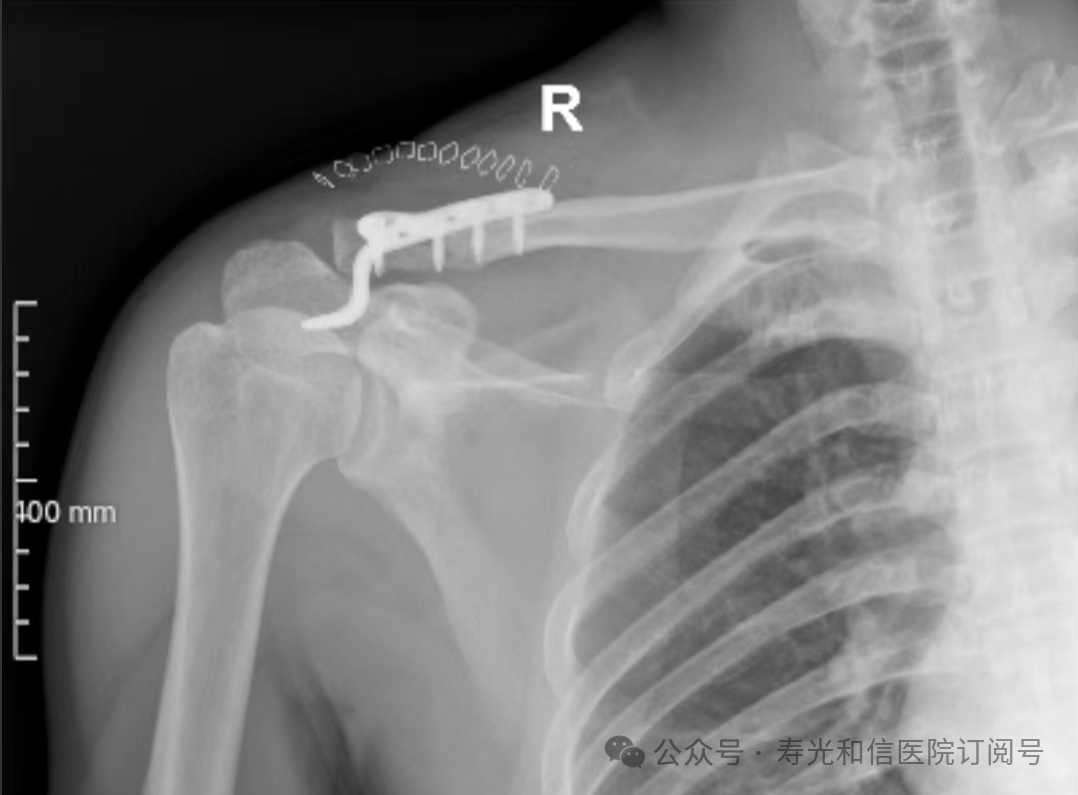

患者经120接诊,完善相关辅助检查后收入寿光和信医院骨外科。检查发现,患者右锁骨骨折、左股骨颈骨折、左大转子撕脱骨折、右膝关节前交叉韧带止点撕脱骨折、右膝关节外侧副韧带损伤、颅骨骨折及全身多处皮肤挫伤。因患者是外地来寿人员,家属短时间内不能赶过来,并且患者家庭经济条件较差,没有缴纳住院手术费的能力。但是股骨颈骨折后,股骨头坏死发生几率较高,手术越早进行,越有利于减少发生股骨头坏死的几率。骨外科主任李刚始终牢记救死扶伤的神圣职责,本着为病人负责的原则,坚定地选择先行为患者实行手术治疗。

与患者本人充分沟通后,李刚主任率领骨外科团队,经过充分的术前讨论及术前准备,于2024年9月1日为患者在全身麻醉下实施了4个半小时的内固定手术治疗。“时间就是生命”,手术过程中,全体参与人员密切观察病情变化,敏锐发现早期异常指标,争分夺秒,一丝不苟地做好各项抢救救治工作,做到瞬间判断、正确评估、果断处理,赢得了抢救患者的“黄金时机”,确保了手术的顺利完成。

在为其进行股骨颈骨折治疗时,手术团队为其采取了股骨颈动力交叉钉系统,这是一种新型股骨颈内固定系统,属微创植入,较从前的技术具有手术时间短、创伤小、力学稳定、滑动加压等优点。同时,患者恢复快,可早期离床、不负重下活动,缩短住院时间及康复时间,有效降低患者股骨颈骨折不愈合发生率,降低长期卧床合并症和死亡率。